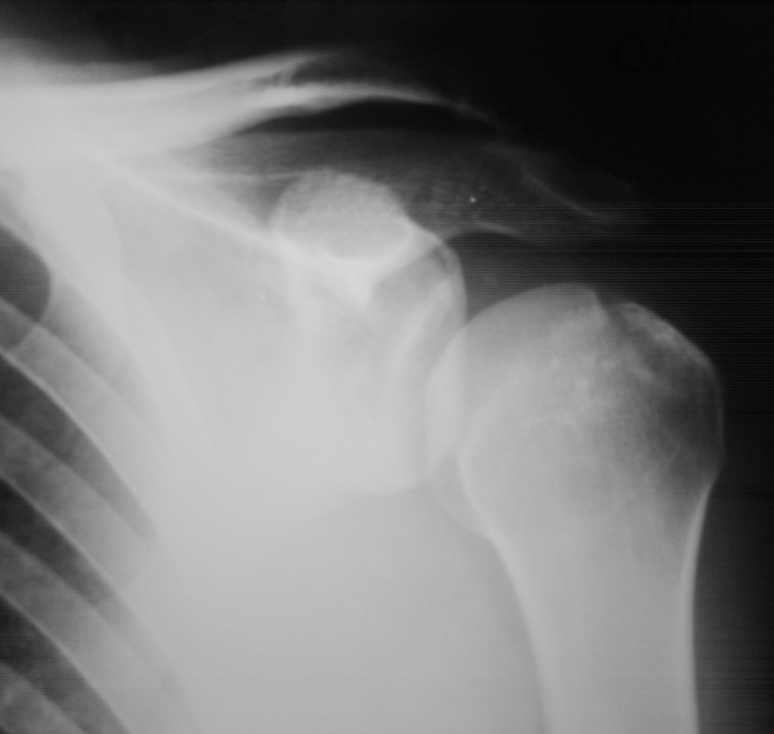

Падение на очередной гонке. По рассказу пациента произошел вывих плеча, который доблестные мед. работники города Саранска вправили "наживую" прямо на стадионе. Больного не фиксировали. По приезду зафиксировали плечо в наружной ротации (см. фото). Сделали Кт (На серии КТ с толщиной срезов 3 мм в левой плечевой кости определяется отрыв большого бугорка, определяется линейный перелом клювовидного отростка левой лопатки без смещения отломков (стрелки). В полости сустава- небольшое количество жидкости. В головке плечевой кости определяется эностоз. Определяется краевые костные разрастания акромиального конца ключицы.Заключение: перелом левой лопатки и плечевой кости.)Возникли вопросы по дальнейшей фиксации: Стоит ли давать отведение?Ну и дальнейшая тактика ведения больного.Спасибо за внимание.

В этом случае консервативная терапия наиболее оптимальный метод лечения. Судя по снимку перелом большого бугорка без смещения.Отведение не обязательно. Через 3 недели приступить к разработке движений в суставе. Прогноз благоприятный.